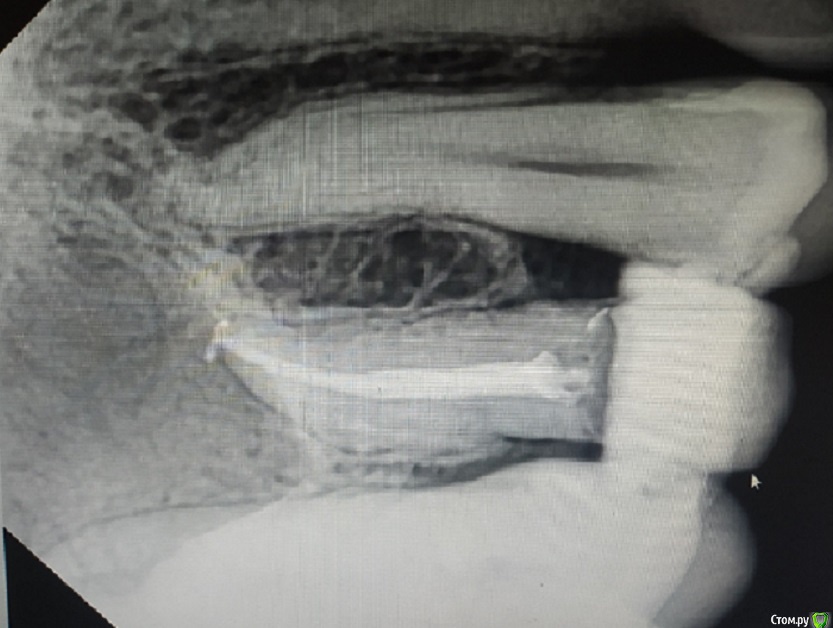

29.07.2019 в 20:35, kuziy12 сказал:

Ортопедия...

Изначальная ситуация:

post-52119-0-27043000-1564421516_thumb.jpg

post-52119-0-52272000-1564421532_thumb.jpg

Преп:

post-52119-0-49731400-1564421552_thumb.jpg

Фиксация:

post-52119-0-44541500-1564421590_thumb.jpg

По поводу цвета...Я настаивал на коррекции, пациент сказал, что его все устраивает и менять ничего не нужно. От проф. гигиены отказался.

А цвет, очень даже подходит, особо под подгнивший моляр.